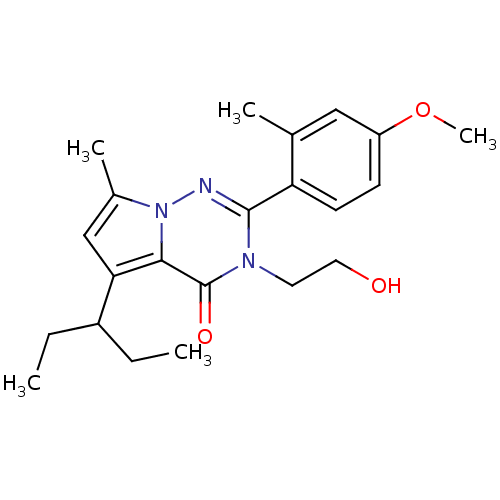

TargetCorticotropin-releasing factor receptor 1(Homo sapiens (Human))

Dupont Pharmaceuticals

Curated by ChEMBL

Dupont Pharmaceuticals

Curated by ChEMBL

Affinity DataEC50: 0.300nMAssay Description:Antagonist activity at human CRF1 receptor expressed in CHO-K1 cells assessed as CRF-stimulated cAMP accumulation by enzyme immunoassayMore data for this Ligand-Target Pair

Affinity DataEC50: 0.420nMAssay Description:Antagonist activity at CRF-R1 in mouse AtT-20 cells assessed as inhibition of human CRF induced cAMP accumulation after 30 mins by radioimmunoassayMore data for this Ligand-Target Pair

Affinity DataEC50: 0.440nMAssay Description:Antagonist activity at CRF-R1 in mouse AtT-20 cells assessed as inhibition of human CRF induced cAMP accumulation after 30 mins by radioimmunoassayMore data for this Ligand-Target Pair

Affinity DataEC50: 0.450nMAssay Description:Antagonist activity at CRF-R1 in mouse AtT-20 cells assessed as inhibition of human CRF induced cAMP accumulation after 30 mins by radioimmunoassayMore data for this Ligand-Target Pair